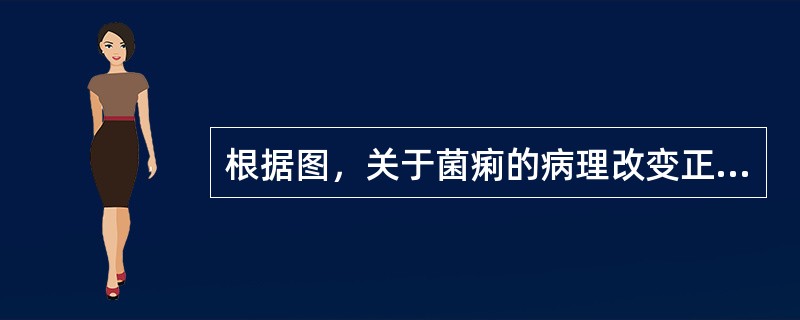

根据图,关于菌痢的病理改变正确的是()

A.黏膜充血、水肿、中性粒细胞和巨噬细胞浸润

B.粘膜下层、肌层、浆膜层有明显的炎症反应

C.假膜主要为纤维素、坏死的肠粘膜、细菌、嗜中性粒细胞及红细胞等,部分有脱落

D.整个肠粘膜有假膜覆盖,粘膜上皮及腺体大片消失

E.大约一周左右,假膜开始脱落,形成大小不等,形状不一的“地图状”溃疡如图